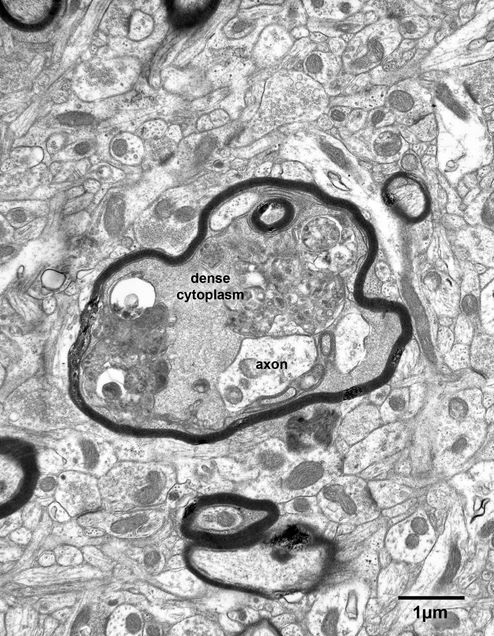

Figure 6.1

A split myelin sheath surrounding an axon in layer 4 of area 46 in prefrontal cortex of a 35 year old monkey. The split has occurred along the major dense line of the sheath, and it contains some dense cytoplasm that must belong to the parent oligodendrocyte.

Figure 6.3

A bundle of nerve fibers in layer 4 of the primary visual cortex of a 30 year old monkey. One of the axons (axon) is surrounded by a sheath that has a large and localized bulge that contains dense cytoplasm. In this example the bulge is produced by the splitting of several lamellae.